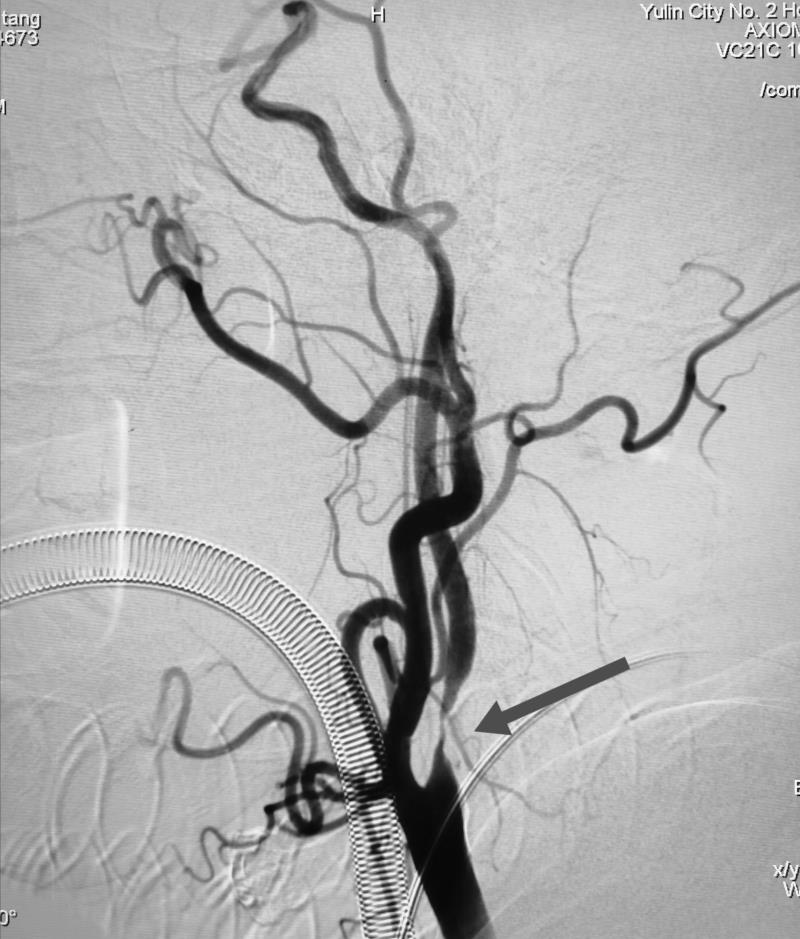

椎基底动脉重度狭窄

颈内动脉重度狭窄

经全脑血管造影术,发现患者右侧椎动脉V4段重度狭窄,正是病灶责任血管,同时发现右侧颈内动脉起始段重度狭窄。患者王某的情况岌岌可危,这两处血管狭窄随时可能闭塞,一旦闭塞,轻则出现严重残疾,完全丧失生活能力,重则很快危及生命,他的椎动脉远端狭窄处介入手术风险异常高,手术过程中很可能发生急性血管破裂或栓塞,形成严重的脑干出血或者梗死,造成死亡。患者右颈内动脉狭窄处于颈动脉窦部,是人体血压和心率的感应器,非常敏感,加之该患者平时就有心率缓慢的情况,术中很有可能心脏停搏造成死亡。

术中放置起搏器

术中,榆林二院心血管介入团队给患者放置心脏临时起搏器,为心脏保驾护航;麻醉科给予患者妥善全麻后,由榆林二院脑科医院神经内科一病区联合神经外科一病区,经过娴熟、精准的操作,顺利完成手术,术中术后未发生任何并发症。